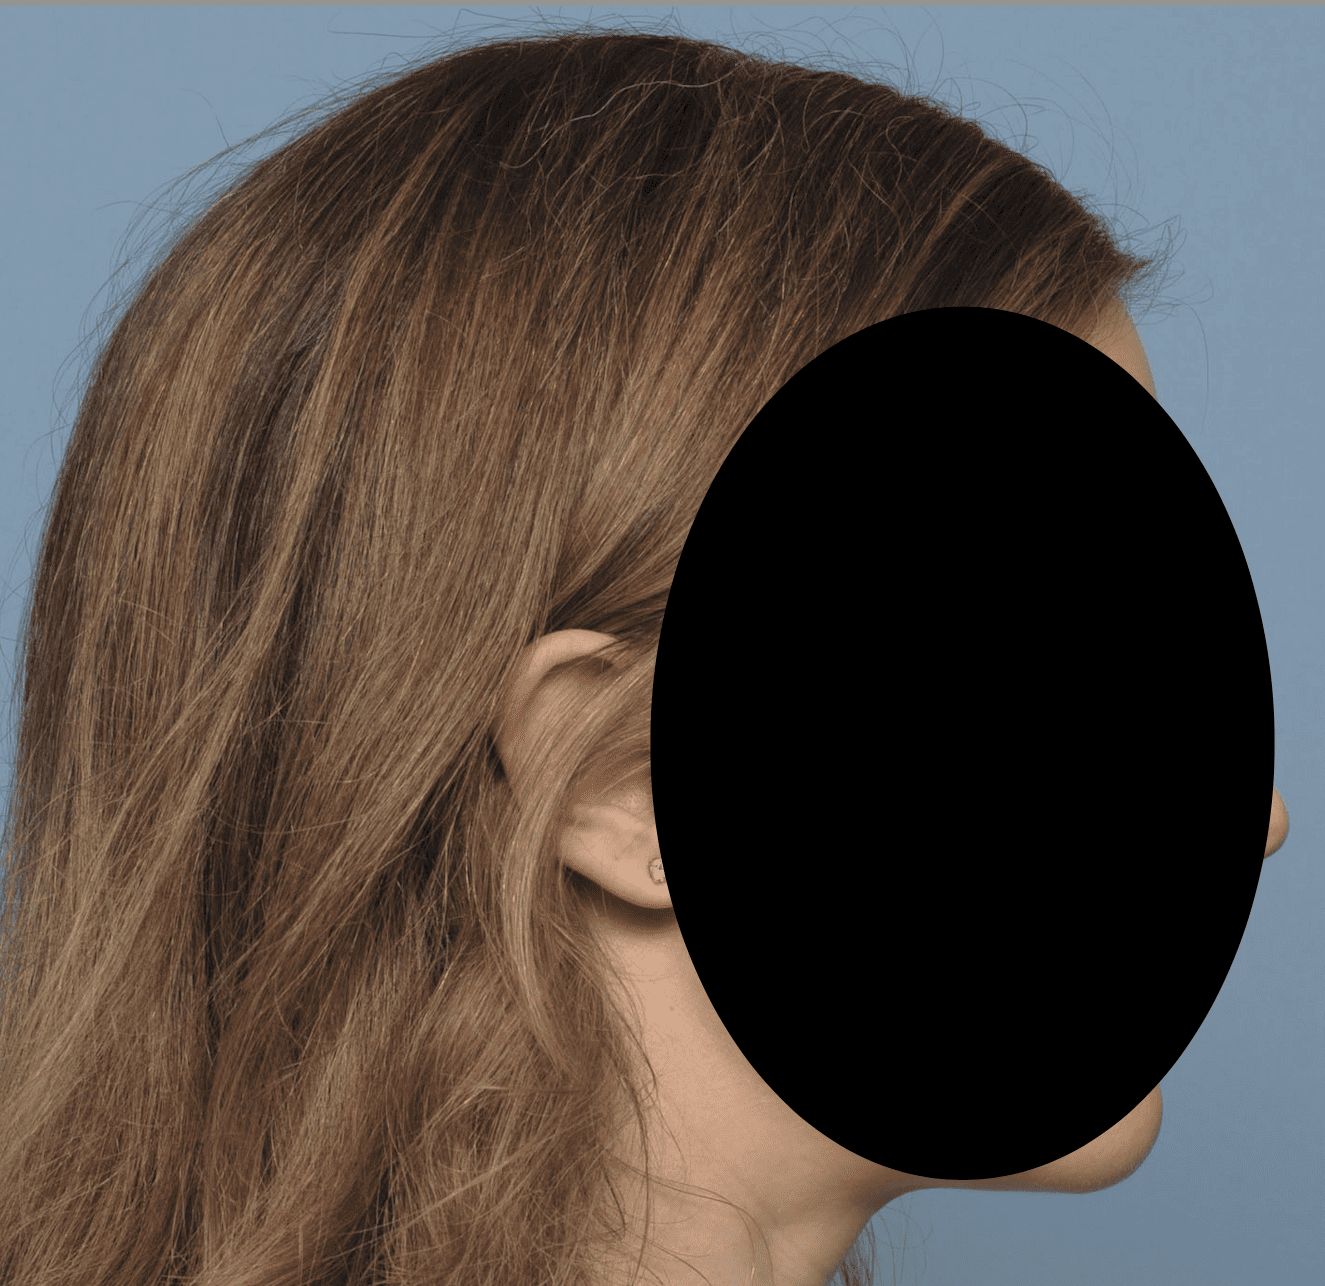

Desire for a higher and more prominent crown of the skull.

Crown of skull augmentation using a custom skull implant.

Desire for a higher and more prominent crown of the skull.

Crown of skull augmentation using a custom skull implant.